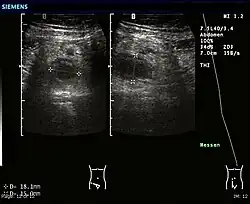

Abdominal ultrasonography, preferably with doppler sonography, is useful to detect appendicitis, especially in children. Ultrasound can show the free fluid collection in the right iliac fossa, along with a visible appendix with increased blood flow when using color Doppler, and noncompressibility of the appendix, as it is essentially a walled-off abscess. Other secondary sonographic signs of acute appendicitis include the presence of echogenic mesenteric fat surrounding the appendix and the acoustic shadowing of an appendicolith.[59] In some cases (approximately 5%),[60] ultrasonography of the iliac fossa does not reveal any abnormalities despite the presence of appendicitis. This false-negative finding is especially true of early appendicitis before the appendix has become significantly distended. Also, false-negative findings are more common in adults where larger amounts of fat and bowel gas make visualizing the appendix technically difficult. Despite these limitations, sonographic imaging with experienced hands can often distinguish between appendicitis and other diseases with similar symptoms. Some of these conditions include inflammation of lymph nodes near the appendix or pain originating from other pelvic organs such as the ovaries or Fallopian tubes. Ultrasounds may be either done by the radiology department or by the emergency physician.[61]

-

Ultrasound showing appendicitis and an appendicolith.[62]

Ultrasound showing appendicitis and an appendicolith.[62] -

Ultrasound of a normal appendix for comparison. -

A normal appendix without and with compression. Absence of compressibility indicates appendicitis.[59]